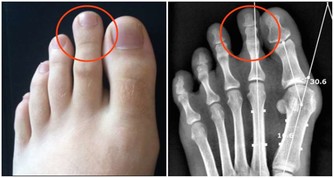

***3、容易抽筋,渾身乏力***

身體抽筋,很多人會默認是缺鈣導致的,但在補充鈣質後仍然反复抽筋,並且還會產生嚴重的疼痛四肢乏力的問題,還應該考慮缺鉀的原因。因為鉀元素能夠在身體內調節平滑肌的收縮,從而改善肌肉運動。但長期缺鉀會導致肌肉收縮異常,導致抽筋,痙攣渾身乏力